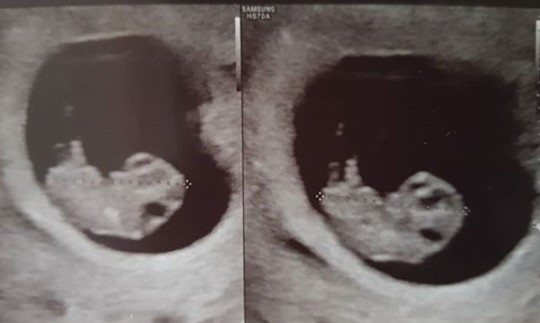

[경북신문사 = 온라인뉴스팀 기자] 배우 윤상현과 가수 겸 작사가 메이비 부부가 셋째 임신 소식과 함께 초음파 사진을 공개해 세간의 관심을 집중시키고 있다.윤상현 측은 28일 메이비가 현재 셋째를 임신 중이라며 올해 말쯤 아이를 품에 안을 예정이라고 전했다.두 사람은 현재 임신 소식에 기쁨을 감추지 못하고 있는 것으로 전해졌다. 더불어 메이비는 모든 활동을 접고 태교에 전념할 것으로 보인다.윤상현과 메이비 부부는 지난 2015년 2월 부부의 연을 맺었으며 그해 예쁜 딸을 품에 안았다. 이어 2016년에 둘째 딸을 낳았다. 윤상현은 자신의 SNS 계정을 통해 딸과의 행복한 일상 등을 공개하며 팬들과 소통하고 있다. 특히 이날 그는 태아의 초음파 사진을 공개해 이목을 끌었다.해당 초음파 사진을 접한 네티즌들은 축하 인사를 이어가고 있다.